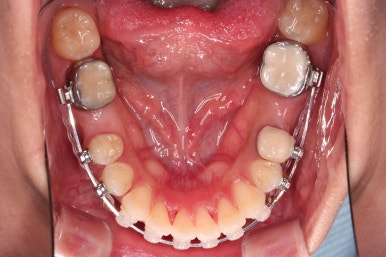

어느새 틈도 다 닫히고요.

마무리 과정만 남았습니다.

틈이 다 없어졌고, 교합도 양호합니다.

무엇보다 임플란트 없이 결손부위가 깔끔하게 채워졌고요.

매우 다행으로 사랑니도 다 있었기 때문에 마치 큰 어금니가 다 있는 것과 같은 상황이 되었습니다.

역설적이게도 손상된 큰 어금니가 없었던 부위는 작은 어금니를 발치함으로 인해 오히려 치아 갯수가 모자라 보이는 상황까지 왔네요.(어금니가 결손된 부분이 더 자연스럽게 보이는 상황)